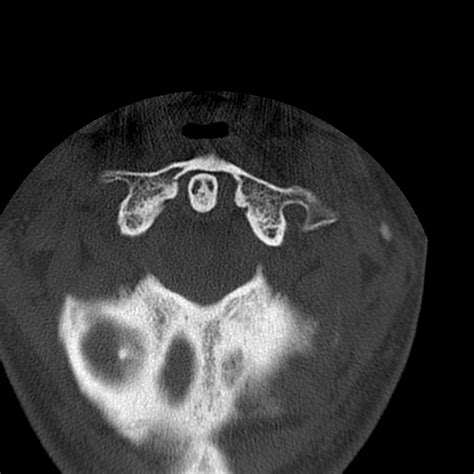

• Computed Tomography (CT) Scan: This is the gold standard for diagnosing occipital condyle fractures. CT scans provide detailed images of the bony structures and can help identify the location and extent of the fracture.

Occipital condyle fractures are classified based on their pattern and mechanism of injury. The most commonly used classification system is the Anderson and Montesano classification, which categorizes these fractures into three types:

Type II Basilar skull fracture extending into the occipital condyle Lateral mass displacement